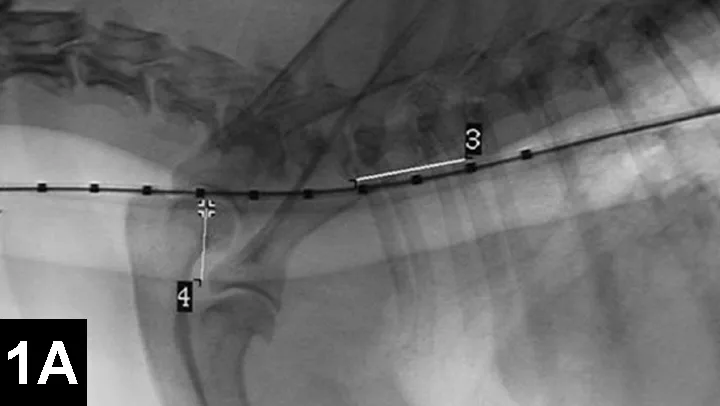

Clinical improvement can be achieved in 75% to 90% of animals treated with self-expanding metallic stents (Figure 1), an IR procedure.4 Immediate adverse events were mostly minor; however, a perioperative mortality rate of about 10% was reported. Longer-term adverse events included shortening of the stent, fracturing of the stent, progressive tracheal collapse, and excessive granulation tissue.

Figure 1A: Serial lateral fluoroscopic images of a dog with tracheal collapse.

A positive pressure ventilation demonstrates maximal dilation of the trachea. A marker catheter in the esophagus is used to account for radiographic magnification.